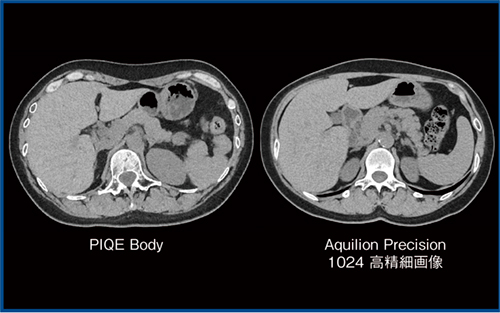

Aquilion ONE / INSIGHT Editionでは,超解像技術「Precise IQ Engine(PIQE)」の腹部領域への適用(PIQE Body),管電圧は70kVを使用可能(従来は80kVまで),最大管電流は1400mAまで出力可能(従来は900mAまで)という3点を実現しており,低管電圧撮影に有効と思われる。なかでもPIQEは,Aquilion Precisionの高精細画像を教師データとしたDeep Learning再構成技術で,1024マトリックスの画像再構成が可能であり,当院の臨床画像の比較でもAquilion Precisionとかなり近似した画像が得られた(図1)。

図1 PIQE BodyとAquilion Precisionの臨床画像(別症例)の比較